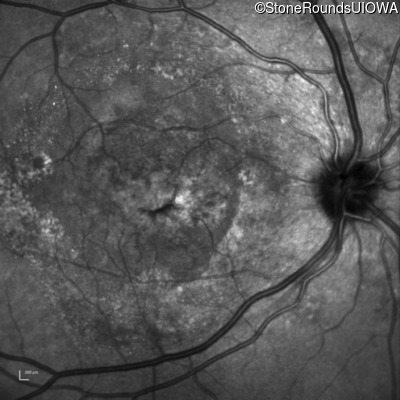

Visit at age: 61 years

Infrared Fundus Photograph - Right - 20/200

Exemplar

Infrared Fundus Photograph - Left - 20/20